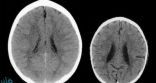

أجرى البروفيسور بروس بيري من مستشفى تكساس للأطفال فحصا ومسحا لدماغي طفلين من نفس العمر، لمعرفة كيف يمكن لطفولة سيئة أن تؤثر على دماغ الشباب.